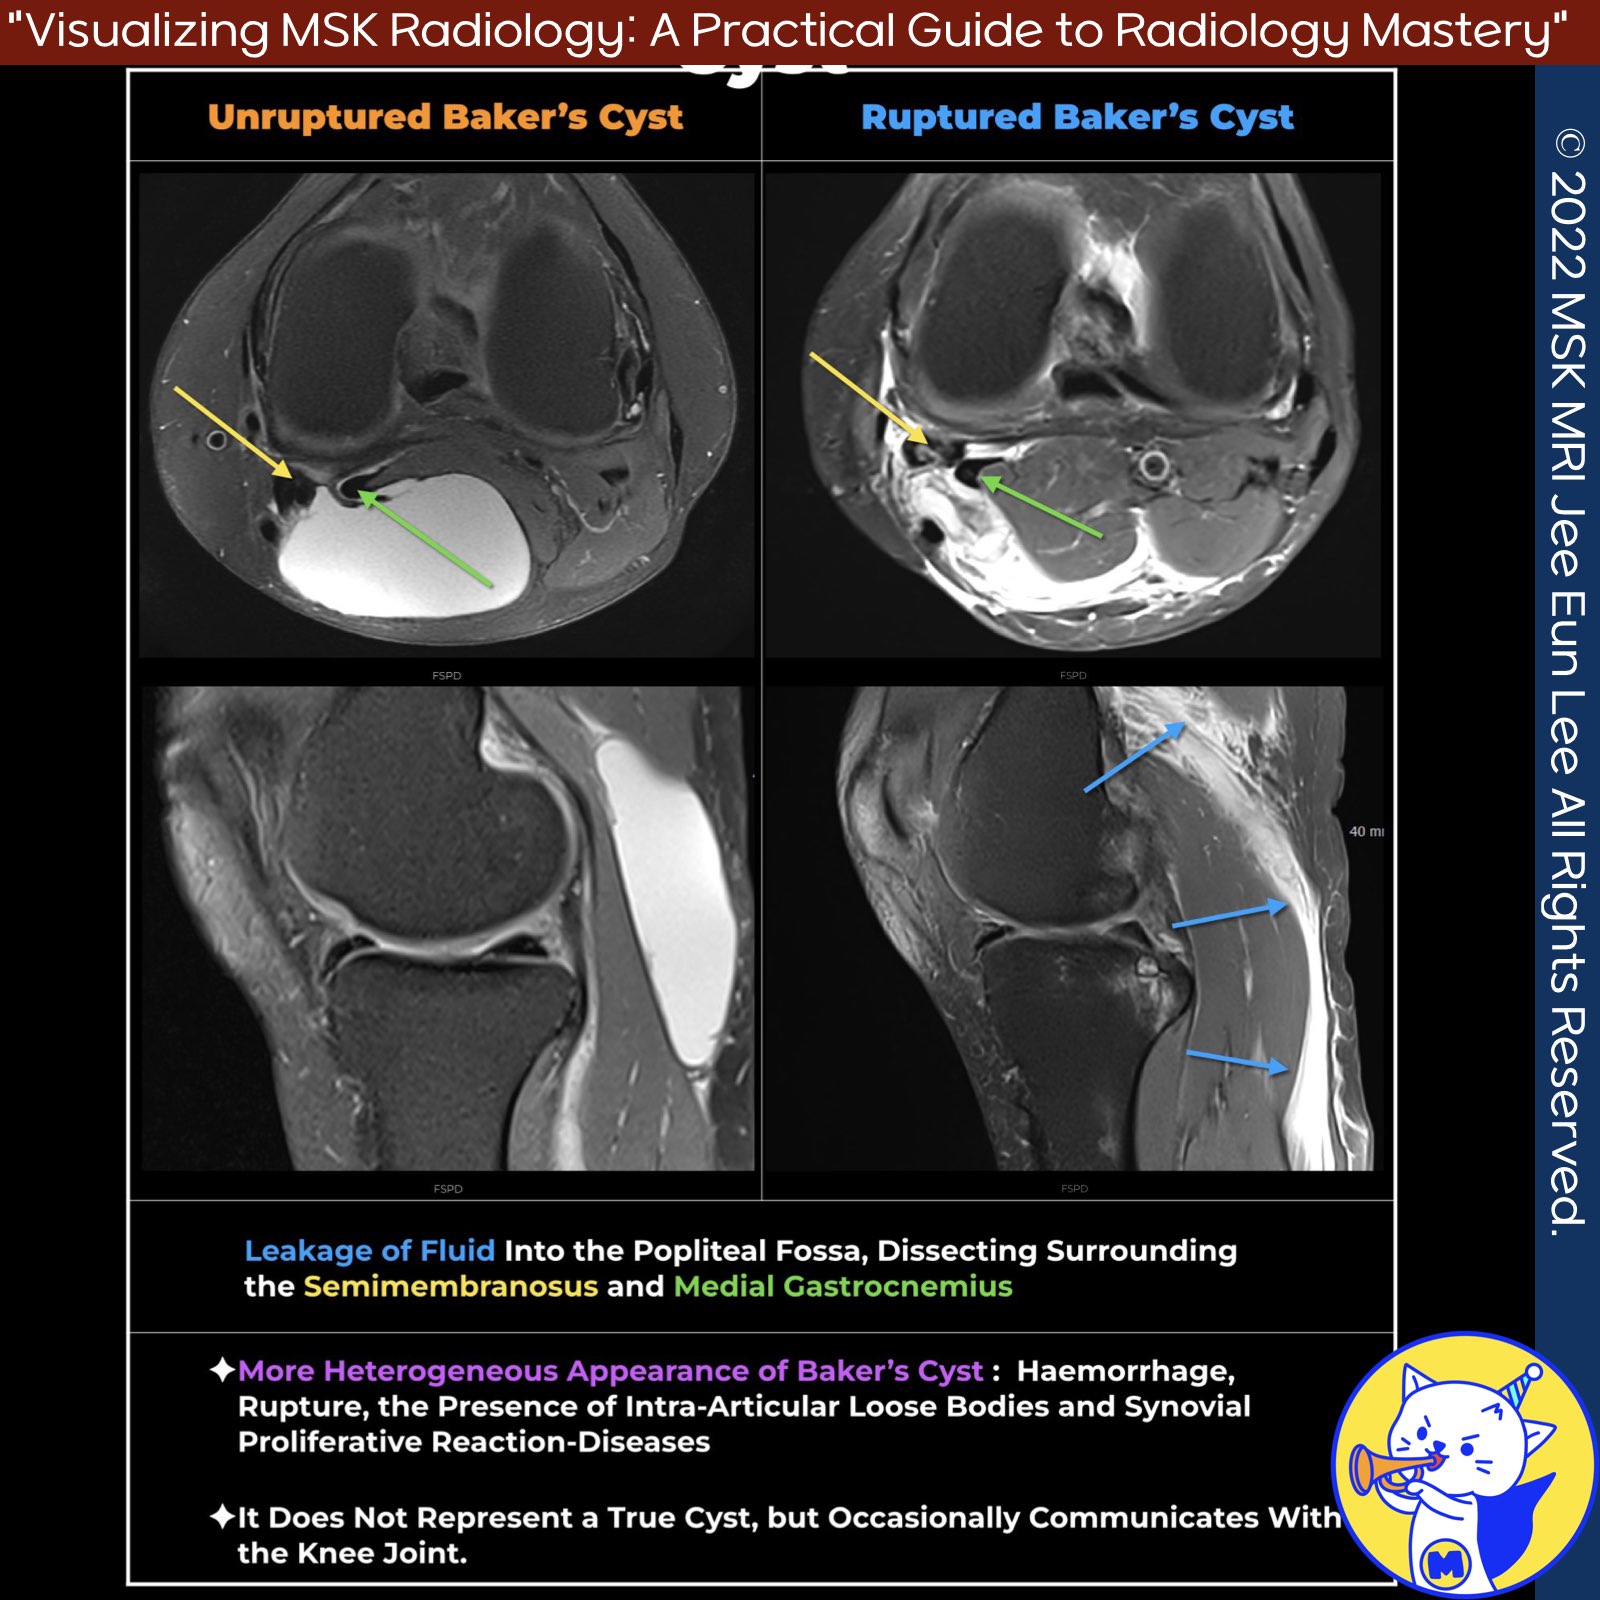

📌 Ruptured Baker’s Cyst

A ruptured Baker’s cyst, also known as a popliteal cyst, is efficiently demonstrated on MRI as a high signal intensity edema dispersing into the adjacent soft tissues and fascial planes on fat-suppressed T2-weighted sequences.

2️⃣ Rupture: Leaking of cyst fluid into the popliteal fossa, between fascial planes, and surrounding the hamstrings and medial gastrocnemius muscles. This is accompanied by edema of the soft tissue and irregularity of the cyst wall .